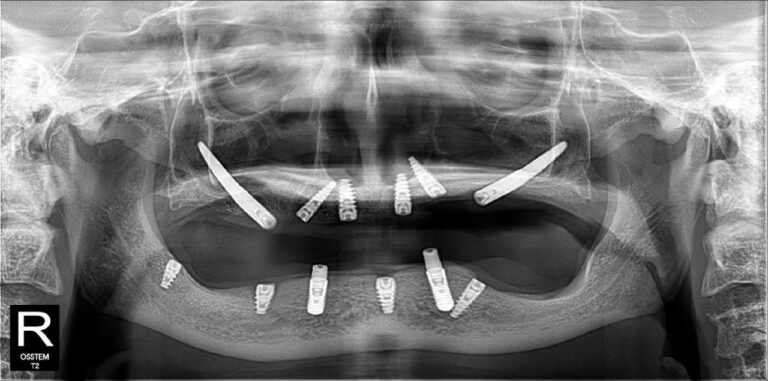

Không nằm ở lời nói mà thể hiện qua kết quả điều trị thực tế. Những hình ảnh X-quang dưới đây là sự khẳng định cho năng lực phẫu thuật và sự chính xác tuyệt đối của BS CKI Nguyễn Trung Khánh trong các ca đại phẫu thuật Implant nhiều lần cắm.